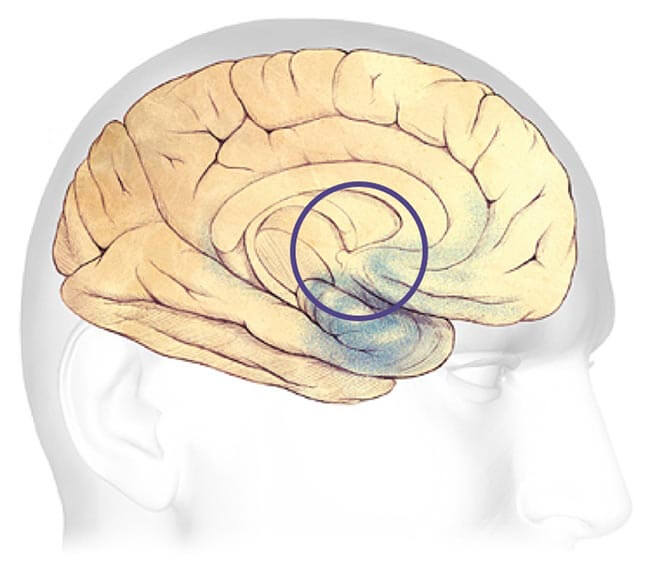

Progression Through the Brain

Plaques and tangles (shown in the blue-shaded areas) tend to spread through the cortex in a predictable pattern as Alzheimer's disease progresses. The rate of progression varies greatly. On average, a person with Alzheimer's lives four to eight years after diagnosis, but can live as long as 20 years, depending on other factors. The course of the disease depends in part on age at diagnosis and whether a person has other health conditions.

Earliest Alzheimer's - changes may begin 20 years or more before diagnosis.

Mild to moderate Alzheimer's stages - generally last from 2 - 10 years.

Severe Alzheimer's - may last from 1 - 5 years.

Earliest Alzheimer's Stages

In the earliest stages, before symptoms can be detected with current tests, plaques and tangles begin to form in brain areas involved in:

Learning and Memory

Thinking and Planning